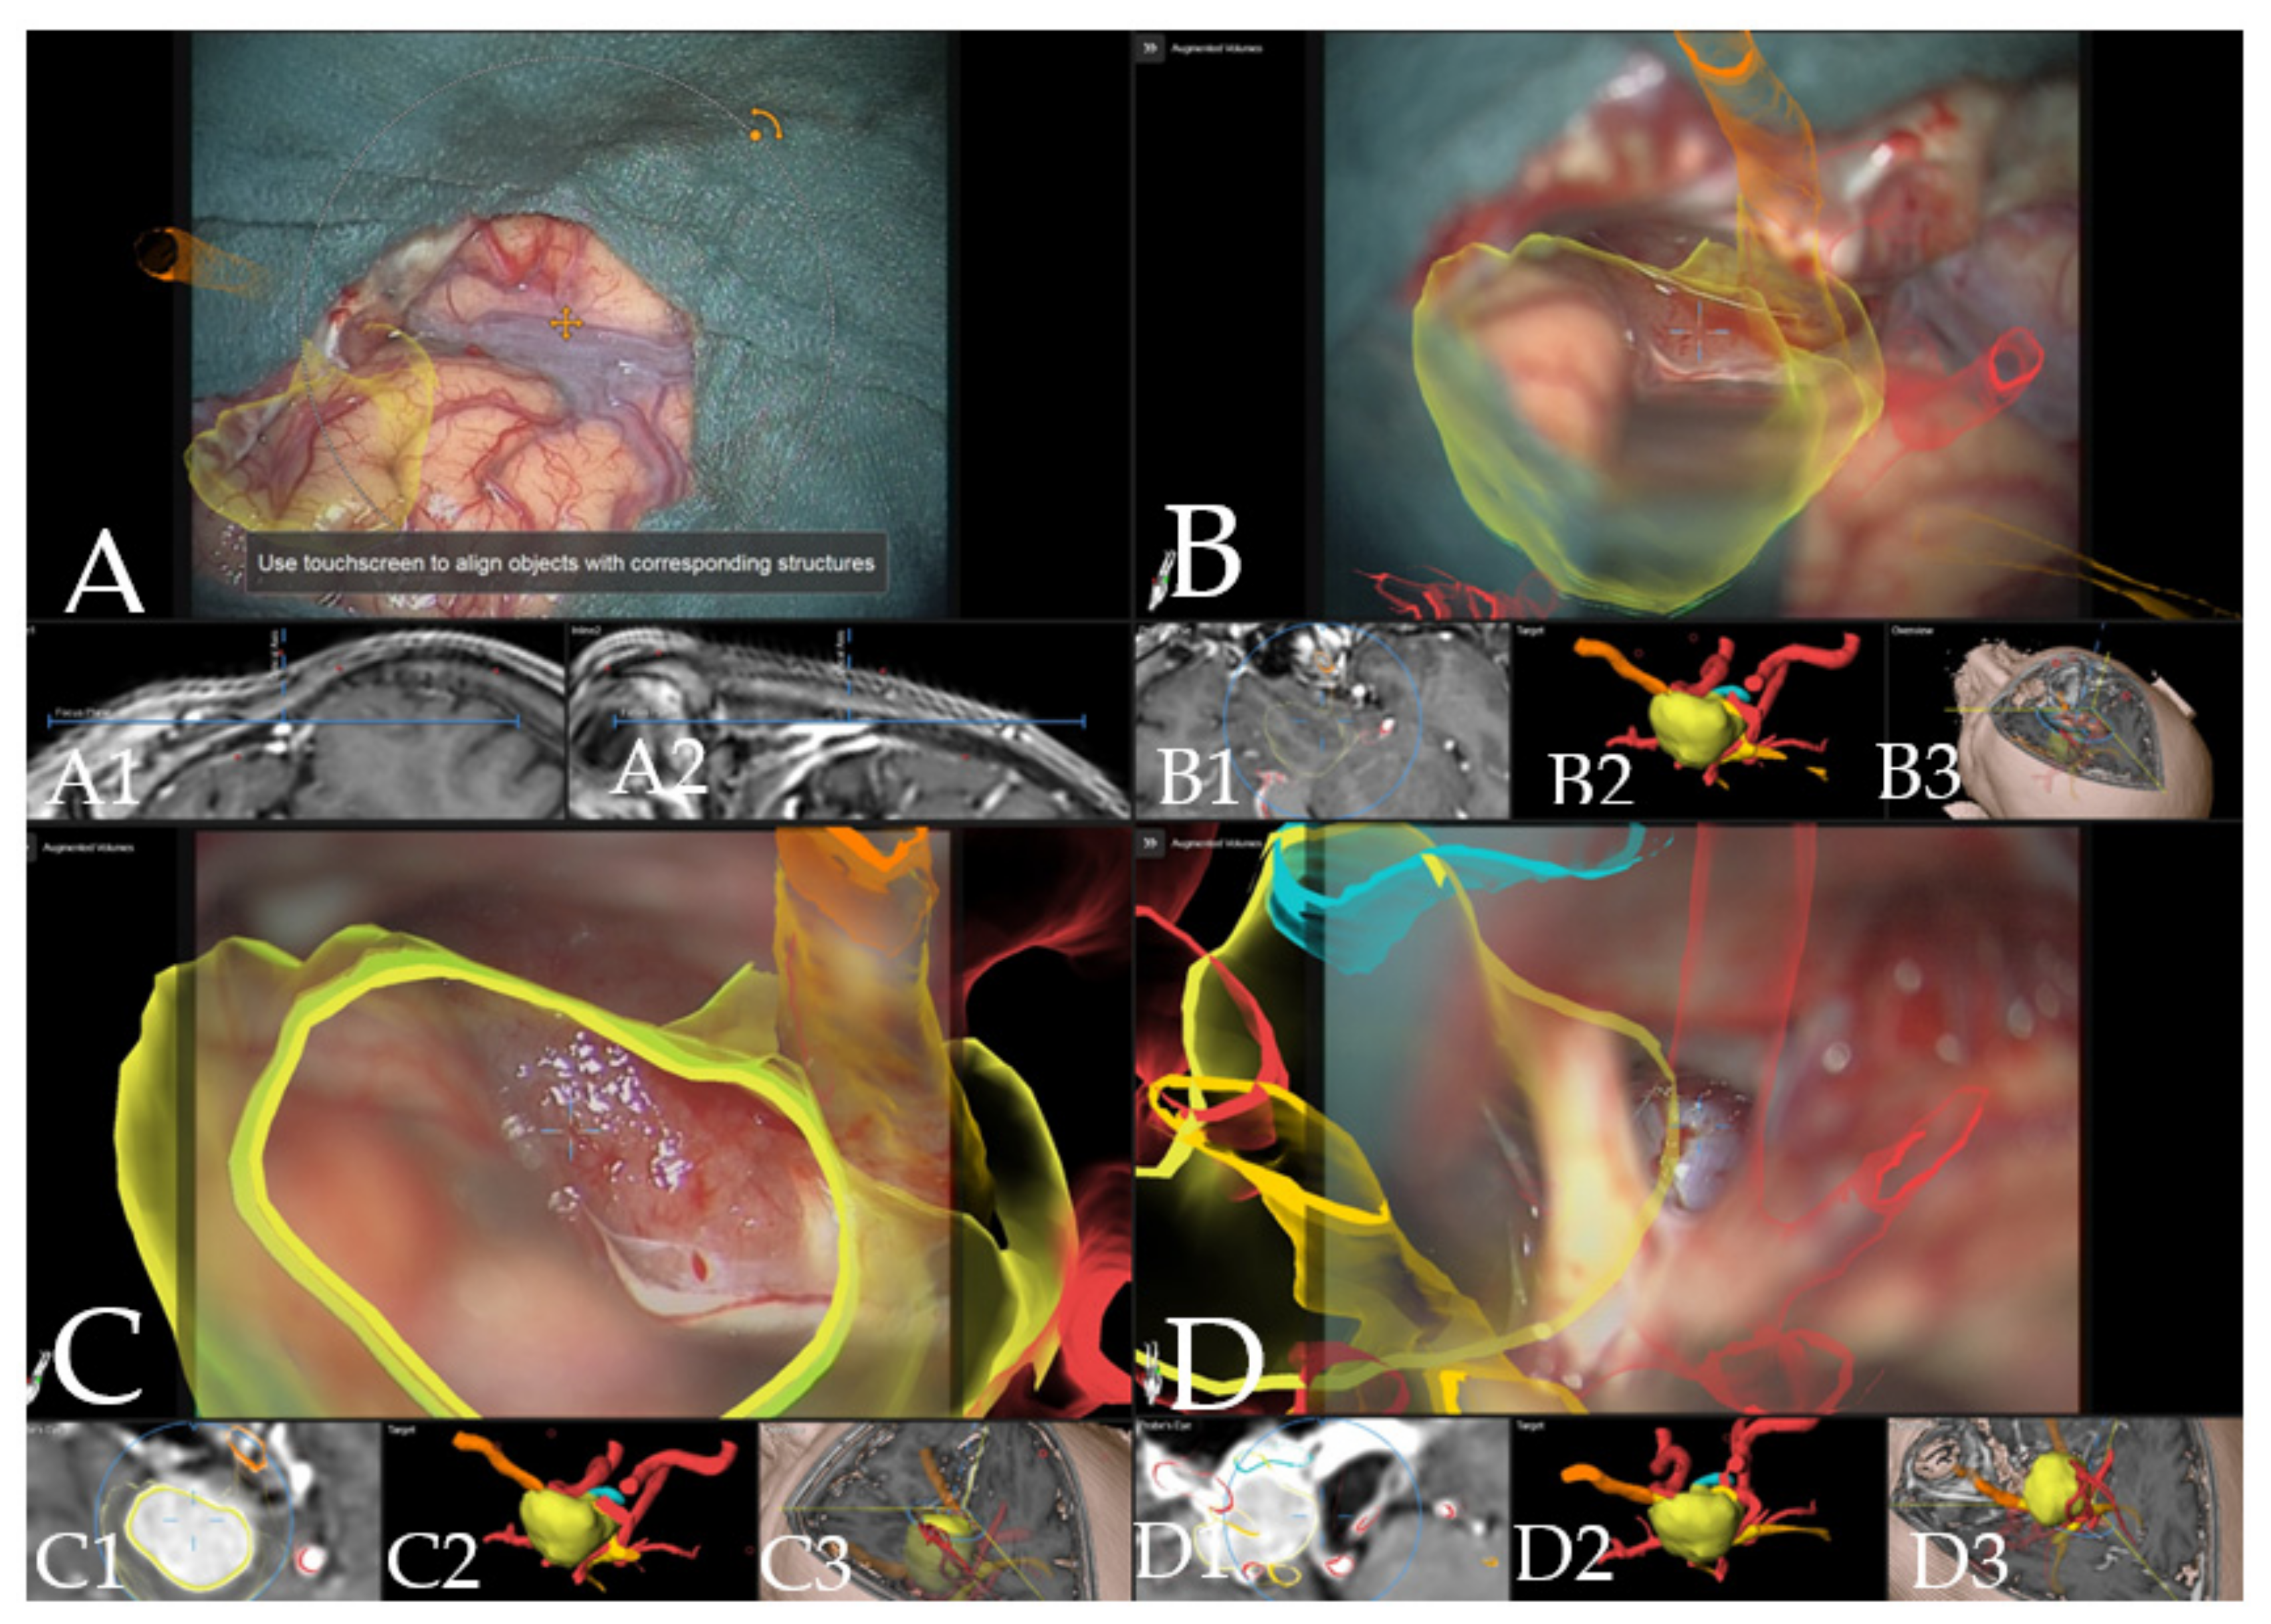

Figure 7. Navigation and augmented reality support during surgery (patient no. 19, same patient as in Figure 1). (A) Three-dimensional visualization of the segmented objects as seen through the microscope video with head up display (tumor in yellow, optic chiasm and optic nerves in orange), showing navigation update after craniotomy with focus on Sylvian fissure in (A1) axial and (A2) coronal view of the standard navigation. (B) Three-dimensional visualization of segmented objects (with vessels in red) following retraction of the frontal lobe with (B1) corresponding probe’s eye view, (B2) target view and (B3) overview depicting the video plane in relation to the segmented objects in 3D fashion. (C) Microscope video of tumor exposure with head-up display with (C1) corresponding probe’s eye view, (C2) target view and (C3) overview of the video plane. (D) AR display on video screen with the 3D outline of tumor, carotid arteries, optic nerves and chiasm with focus on the carotid artery, following complete resection of the tumor with (D1) probe’s eye view, (D2) target view and (D3) overview of the video plane.

Case 3: A 67-year-old female patient (patient number 19) with visual deterioration and bitemporal hemianopsia. MRI showed a suprasellar meningioma which was resected via right pterional approach. Figure 7 demonstrates the visualization of the structures in the AR throughout the surgery.